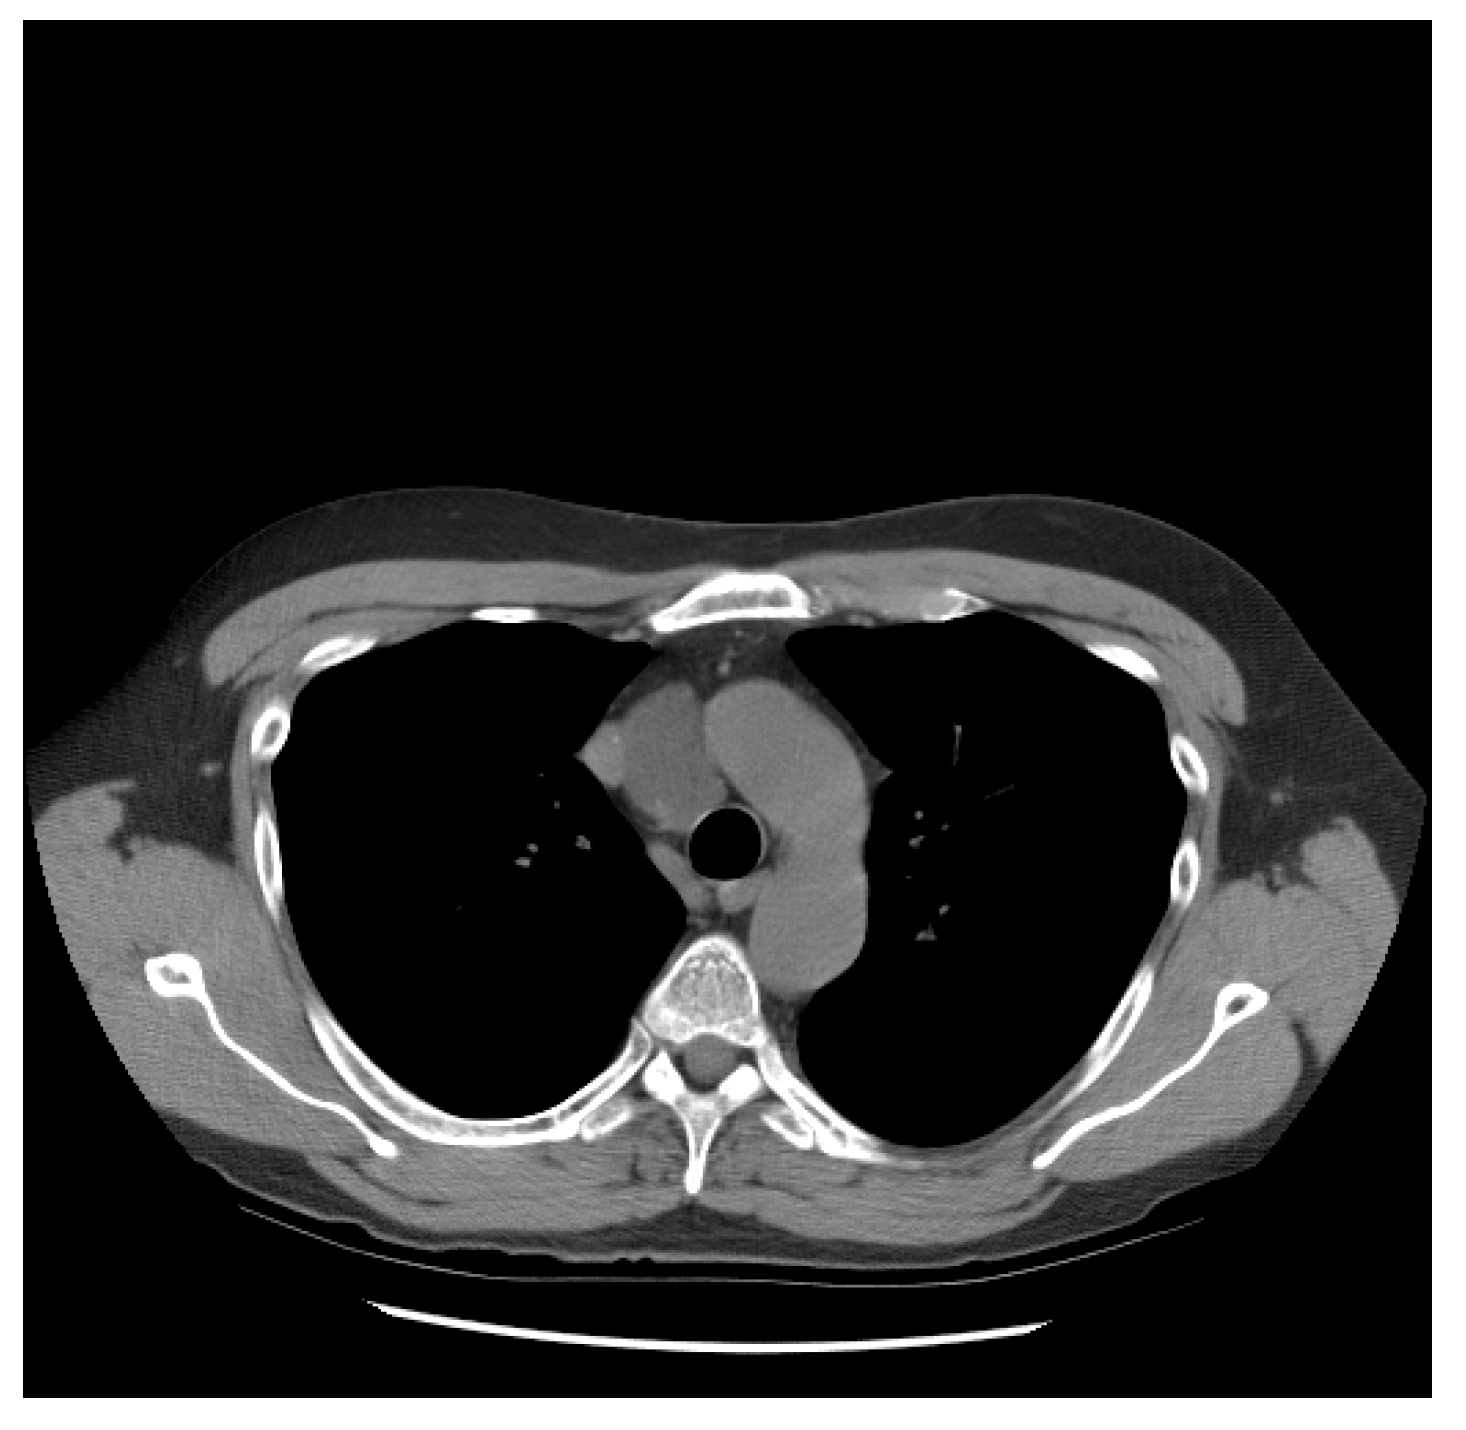

He did well until 21 years following the initial diagnosis, when he presented with a new upper mediastinal mass (Figure 1) and an AFP of 1048 ng/mL. He received paclitaxel, doxorubicin, and gemcitabine (he had a renal transplant due to renal failure after the prior nephrectomy and chemotherapy). Docetaxel replaced paclitaxel due to neuropathy; gemcitabine was removed due to low blood counts.

Figure 1.

Patient S-YST 1 with a new upper mediastinal mass.